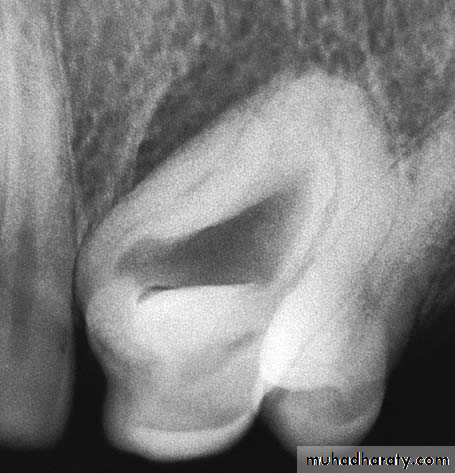

4- Teeth with ankylosed roots or withabnormalities,e.g., dens in dente

4- Extraction of Ankylosed Toothtrapezoidal flap is created, which extends from the lateral incisor as far as the distal aspect of the maxillaryfirst premolar

Removal of the tooth, together with the ankylosed portion of the labial plate

Operation site after placement of sutures

Tooth after removal, with a portion of bone on the labial surface